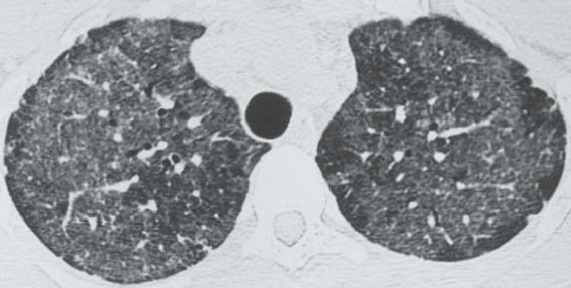

CT

- Patchs de VD bilatéral

- Crazy paving

- Central, péri-hilaire

- Prédominance dans les plages supérieures et péri-hilaire

patchs de VD bilatéraux, lobes sups

patchs de VD bilatéraux, lobes sups